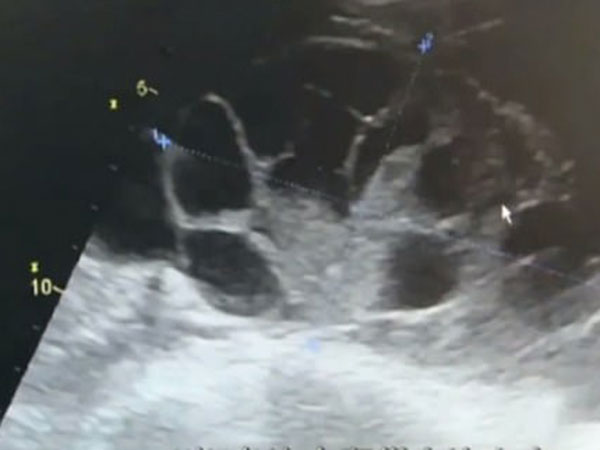

ಈ ಯುವತಿಯಗೆ `ಓವರಿಯನ್ ಹೈಪರ್ಸ್ಟೈಮ್ಯುಲೇಶನ್ ಸಿಂಡ್ರೋಮ್' ಕಾಣಿಸಿಕೊಂಡಿತು. ಈ ಸಮಸ್ಯೆಯು ಗರ್ಭಕೋಶವು ಅತಿಯಾಗಿ ಅಂಡೋತ್ಪತ್ತಿ ಮಾಡಲು ಉತ್ತೇಜಿಸುವ ಸಮಸ್ಯೆಯಾಗಿದೆ ಮತ್ತು ಅದರ ಸುತ್ತಲು ದ್ರವ ಶೇಖರಣೆ ಆಗುವುದು.

ಆಕೆಯ ಹೊಟ್ಟೆಯಿಂದ 5 ಲೀಟರ್ ನಷ್ಟು ನೀರನ್ನು ಹೊರಗೆ ತೆಗೆಯಲಾಯಿತು ಎಂದು ವೈದ್ಯರು ಮಾಹಿತಿ ನೀಡಿದ್ದಾರೆ. ಆಕೆಯ ಗರ್ಭಕೋಶವು 7-8 ತಿಂಗಳ ಗರ್ಭಿಣಿಯರ ಗರ್ಭಕೋಶದಂತೆ ಉಬ್ಬಿ ಹೋಗಿತ್ತು.